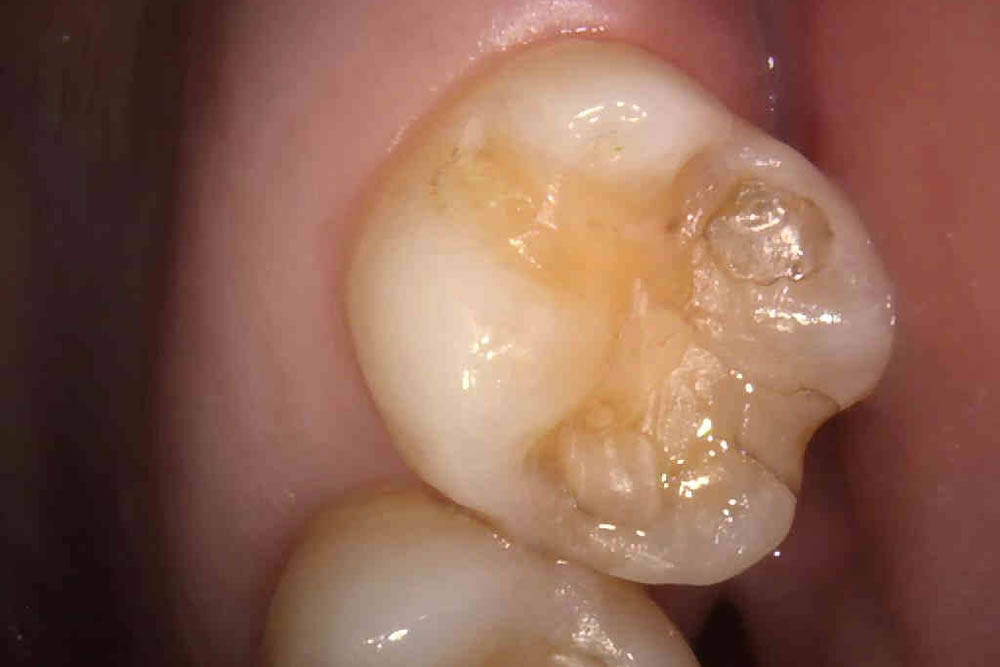

二次むし歯を治療後にセラミックインレーで修復した症例

こちらの症例は、過去に他院にてプラスチックで治療された部位が二次むし歯になっていたため、治療を行った患者さまです。

プラスチックでの治療は小さなむし歯であれば保険診療にて簡易的に治療が可能ですが、完全にむし歯を取り切ったとしても、中でむし歯が再発しやすいというのがデメリットです。

今回はむし歯を取り切った範囲の大きさやむし歯の再発リスクをなるべく下げるため、セラミックインレーでの治療を計画しました。